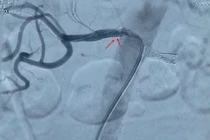

Hẹp động mạch thận là nguyên nhân phổ biến gây tăng huyết áp kháng trị. Can thiệp động mạch thận thoát khỏi những cơn tăng huyết áp kéo dài khó kiểm soát.